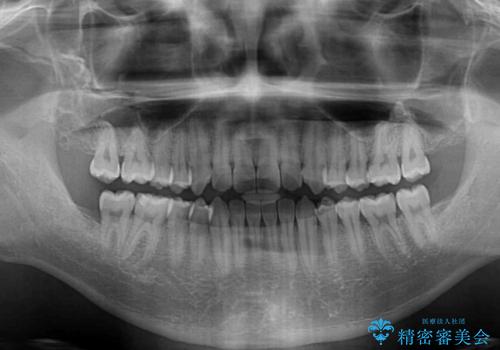

- 上下前歯のデコボコを気にして来院された患者様です。

叢生は軽微であり、費用を抑えて期間もあまりかけずに治療をしたいとのことで、インビザライン・ライトを用いて矯正治療を行うこととしました。

途中通院できなくなり、マウスピースの装着もしっかりとできなかったため、治療期間が長くかかってしまいました。